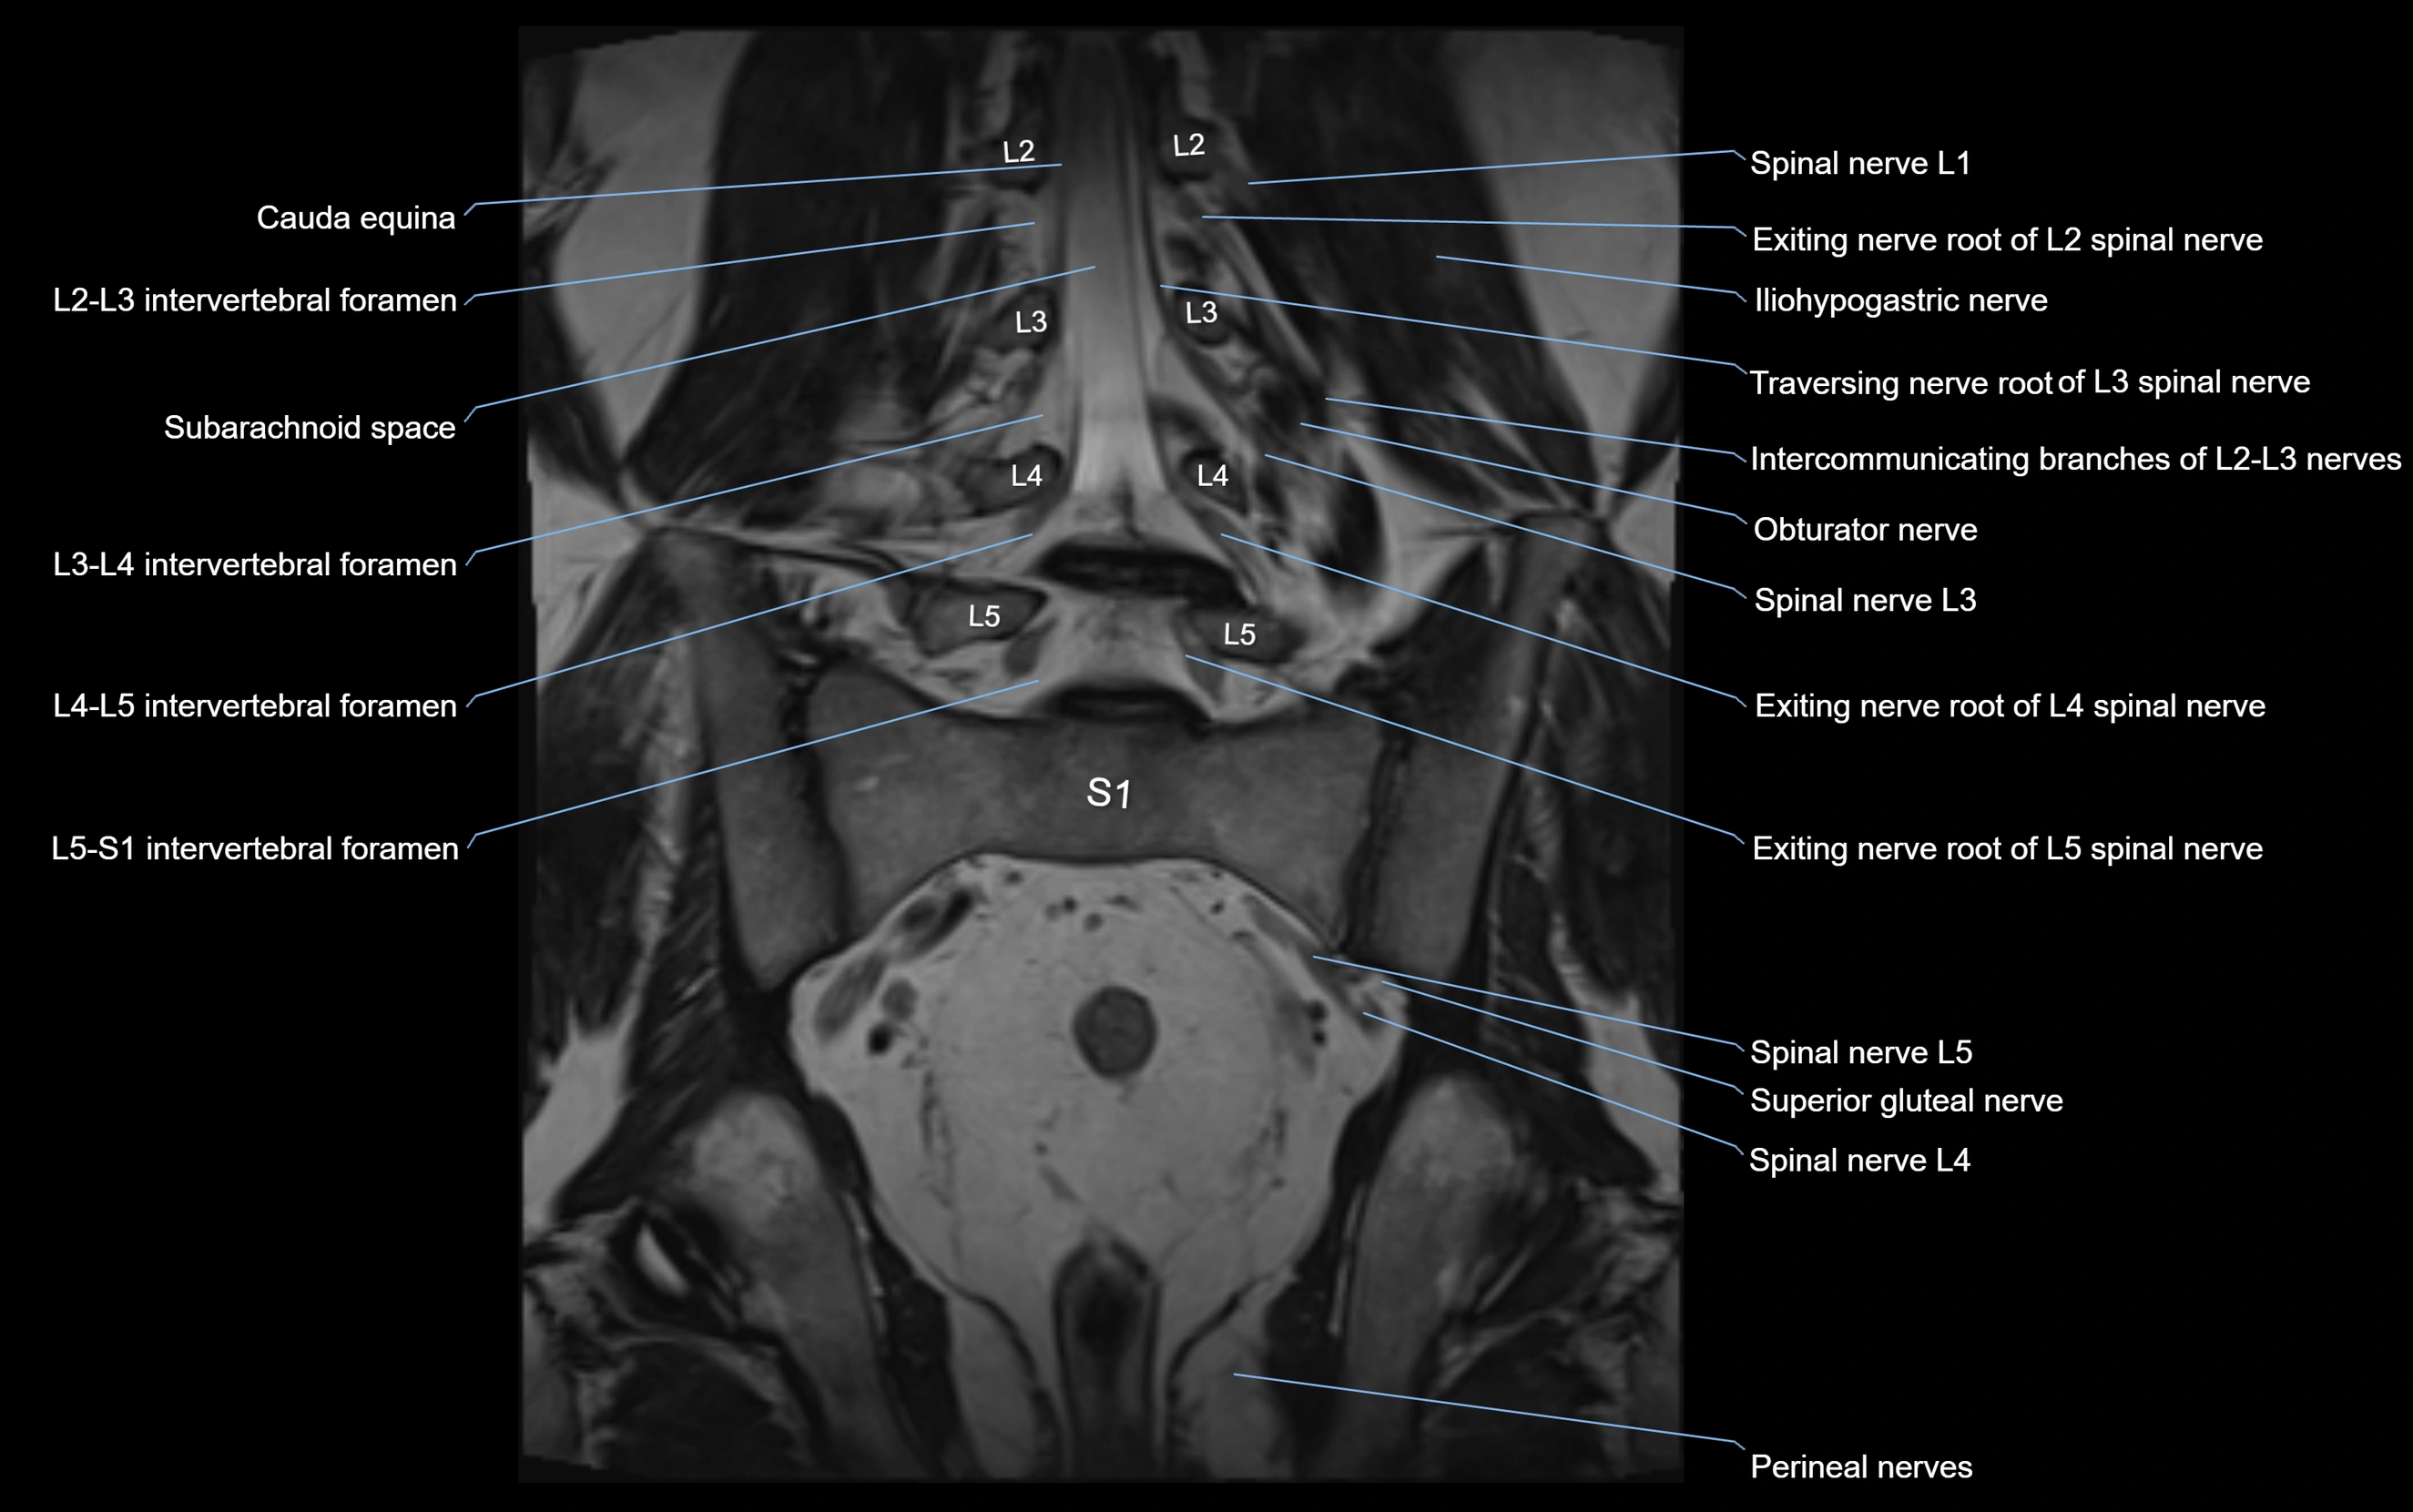

MRI Appearance

T1-weighted images:

• Nerve appears as a very thin low-to-intermediate signal intensity structure

• Surrounded by bright fat, aiding visualization

T2-weighted images:

• Nerve shows intermediate to mildly hyperintense signal compared to muscle

• Pathological involvement appears brighter

STIR (Short Tau Inversion Recovery):

• Normal nerve appears dark

• Inflamed or entrapped nerve appears bright hyperintense

T1 Fat-Sat Post-Contrast:

• Normal nerve enhances minimally

• Pathologic nerve (neuritis, entrapment, tumor infiltration) shows focal or diffuse enhancement

3D T2 SPACE / CISS:

• Nerve appears intermediate to mildly hyperintense compared to muscle

• Surrounded by bright fat or CSF, improving visualization

• Best sequence for mapping small pelvic nerves such as the anococcygeal